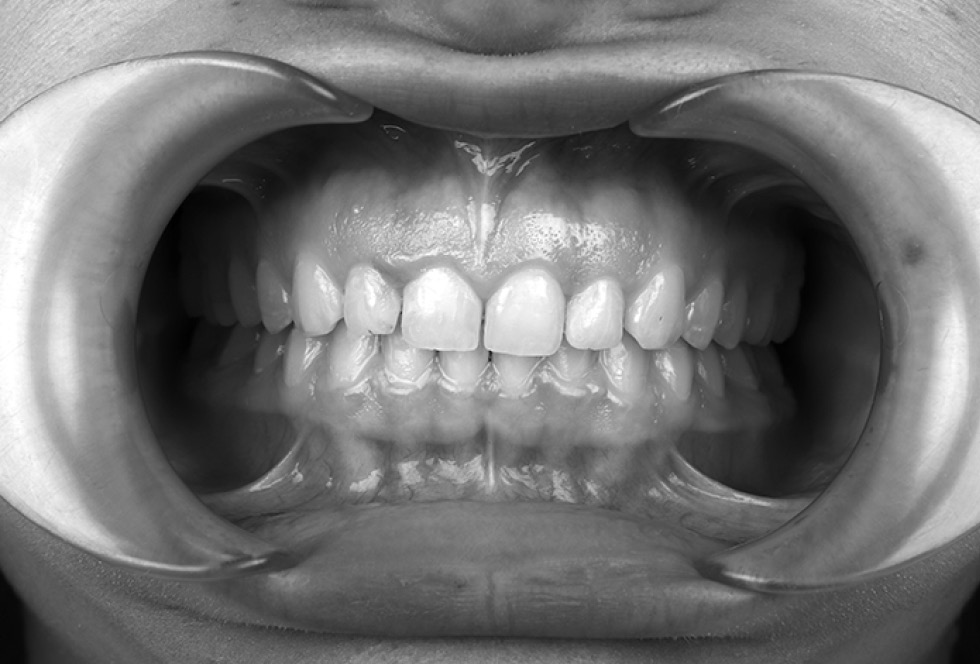

Patient G, 23 years old, presented to the clinic (Figs. 4–6), complaining of pain in the masticatory muscles during the morning and grinding of teeth at night. The examination revealed signs of hypertension in the masticatory muscles. The patient was referred for surface EMG of the masticatory and temporal muscles.

Fig. 6. Intraoral photographs of the patient in occlusion.